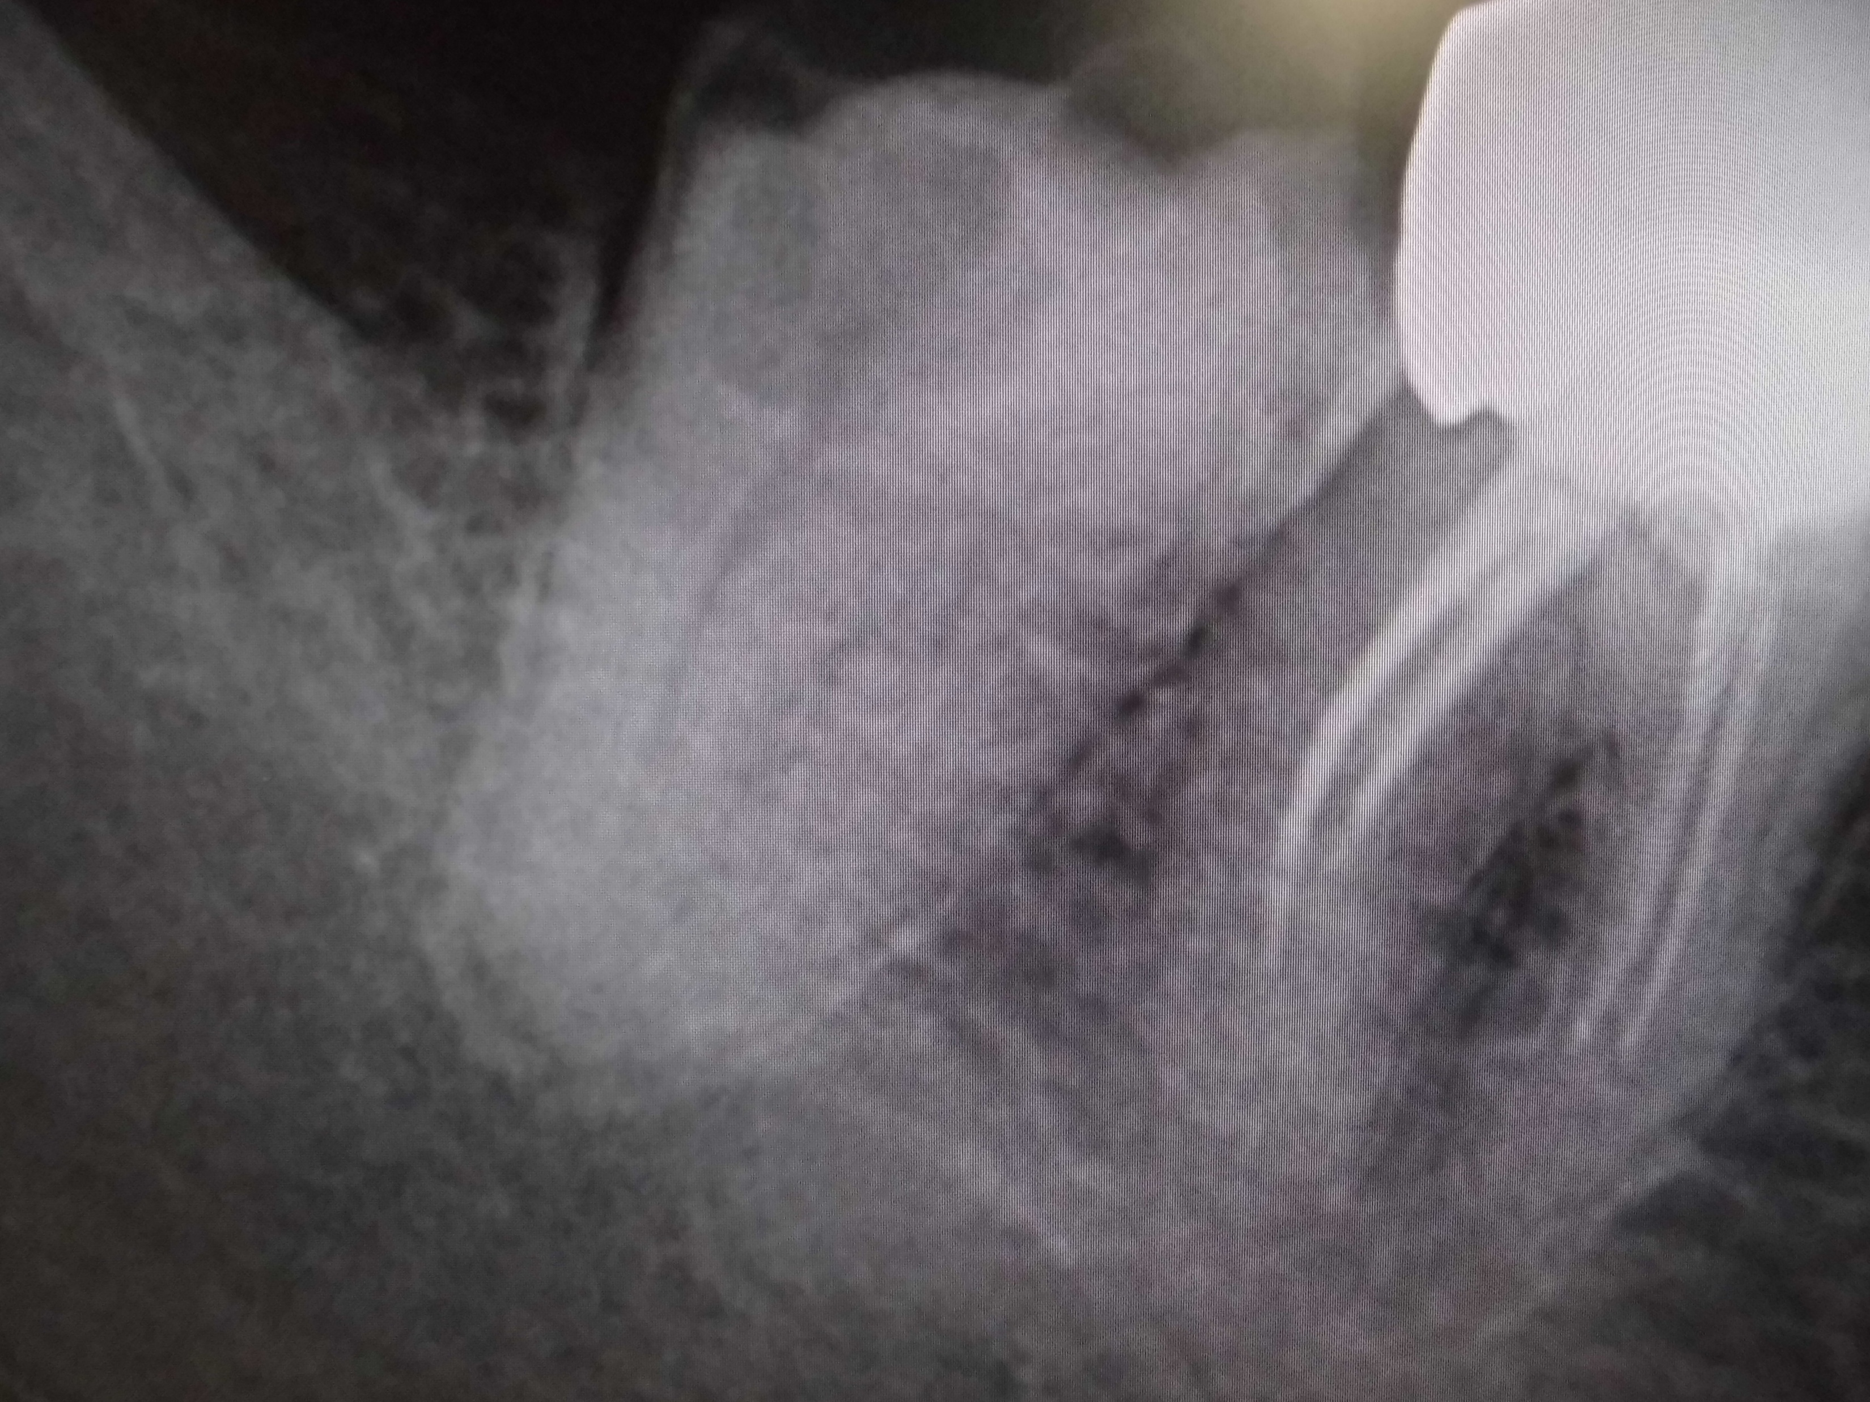

レントゲンでは不明な根尖病巣がCTでははっきり写ります。

同じ患者様です。根管が樋状根になっているのもわかります。